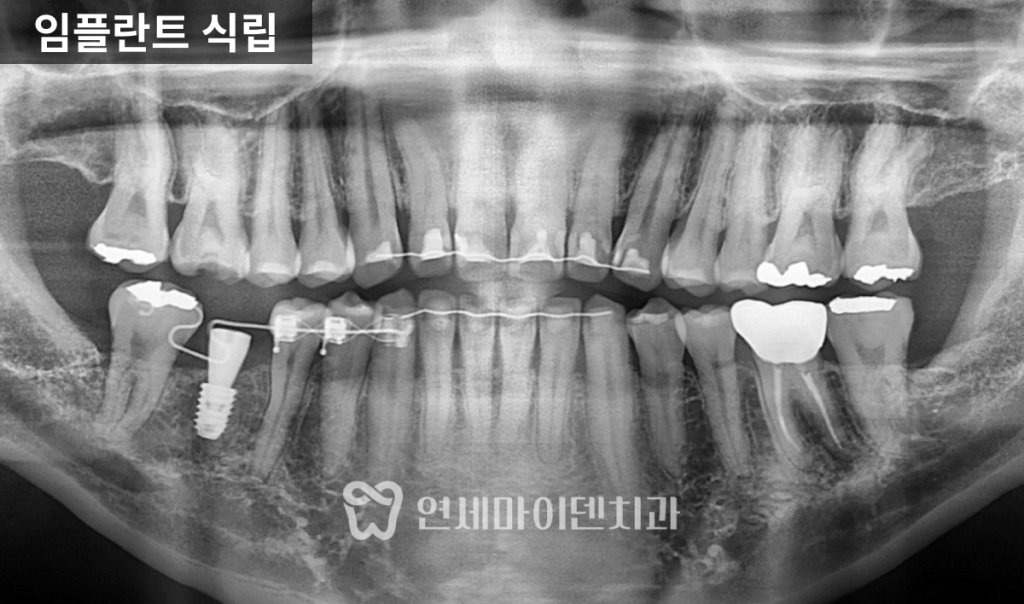

임플란트 식립

공간 확보 후에는 6번 어금니 부위에 임플란트를 식립하였고,

약 2~3개월간의 안정화 기간을 거쳐

뼈와 임플란트가 단단히 결합되었습니다.

이후에는 교정용 철사를 평평한 형태로 교체해

공간 유지와 환자의 편안함을 함께 확보했습니다.

최종적으로는

- 임플란트 크라운이 완성되었고,

- 교합과 주변 치아의 움직임 없이 안정적인 결과를 얻을 수 있었습니다.

또한 왼쪽 아래 어금니의 재신경치료 부위 염증도 호전되어,

전체적인 구강 상태가 크게 개선되었습니다.